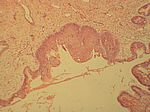

Plattenepithelmetaplasie Cervix, HE